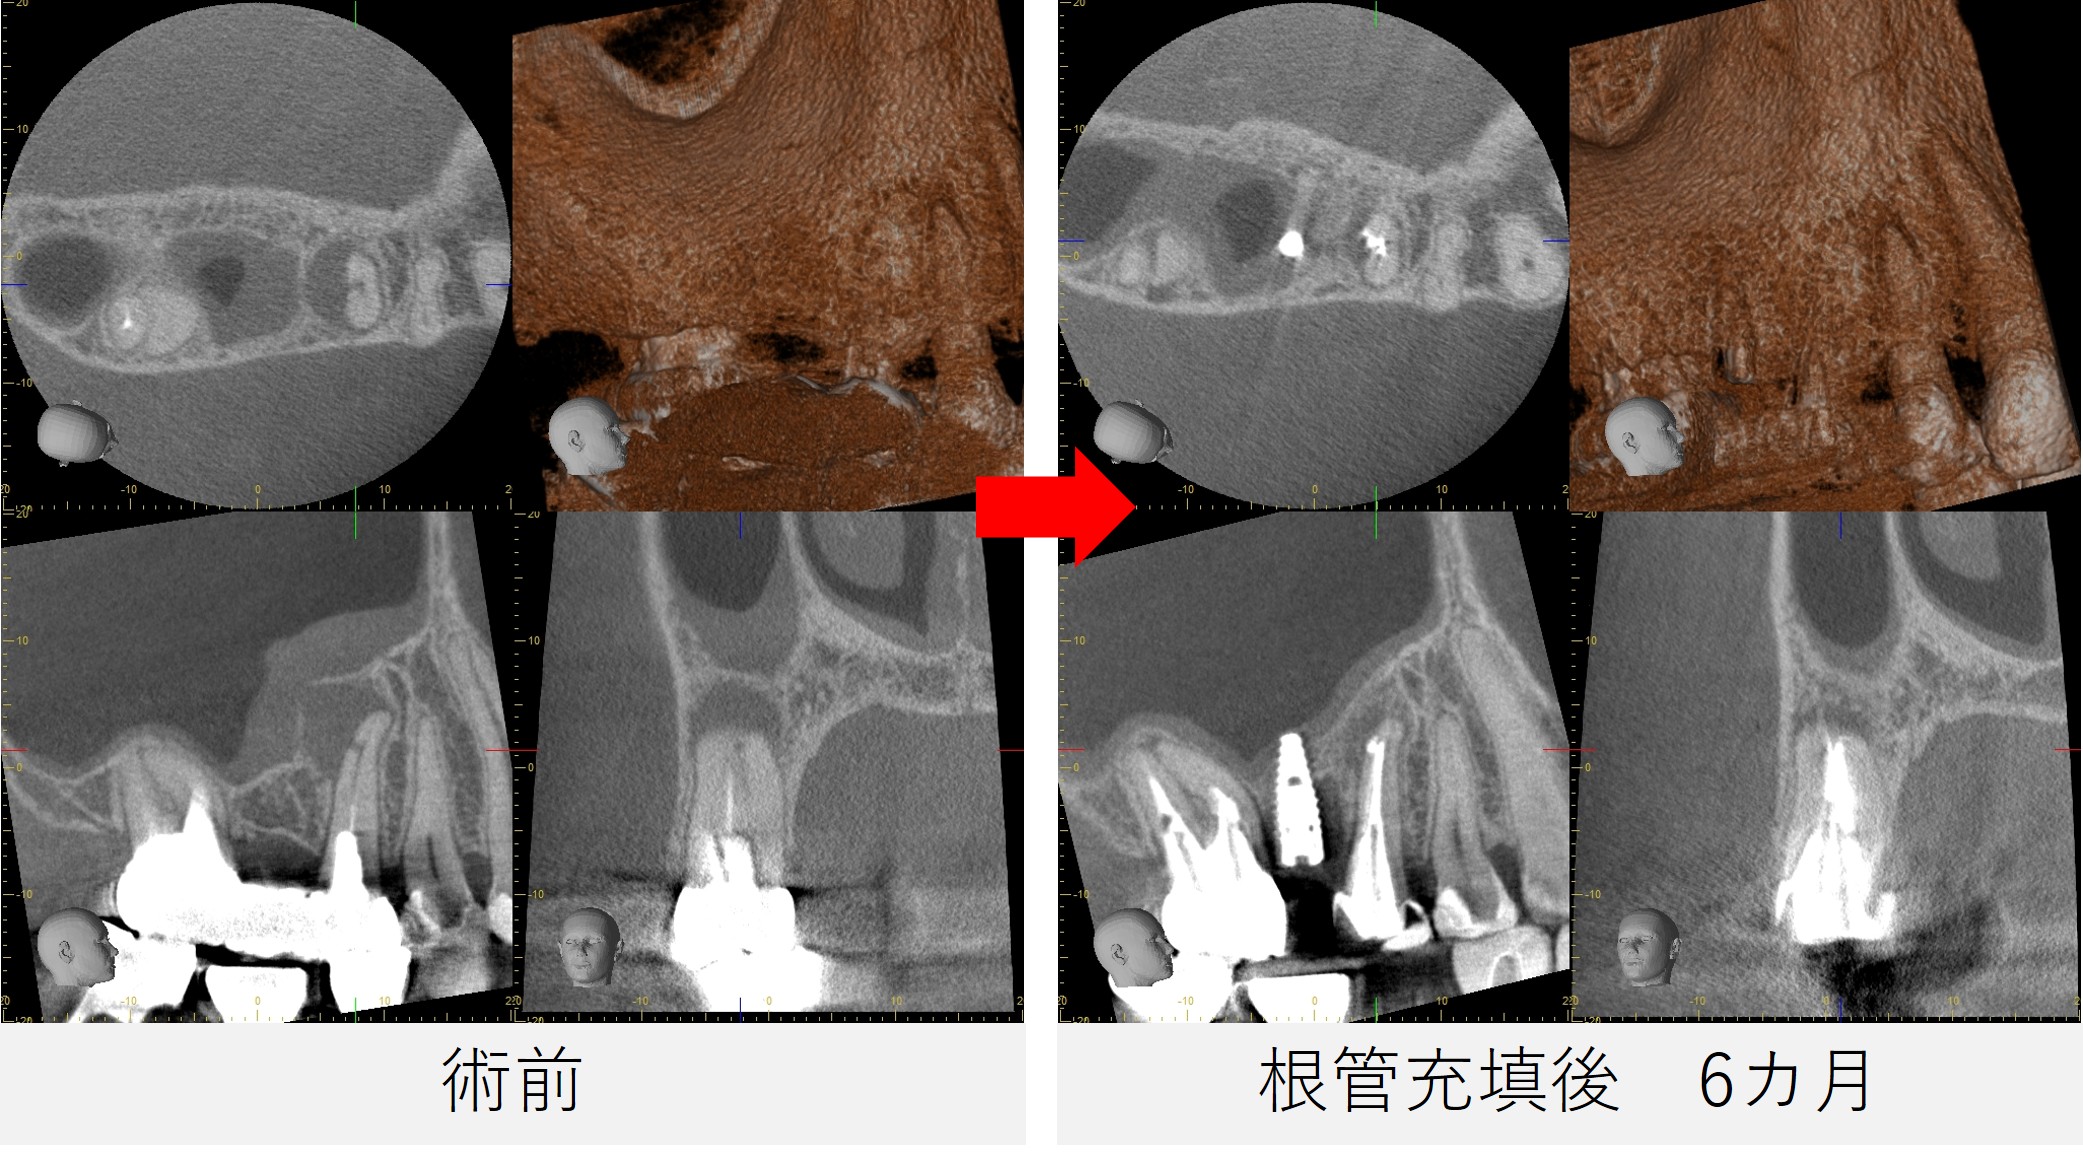

●レントゲン・CT画像所見

レントゲン写真およびCT画像にて、 右上5番の根尖部に黒い影(骨のない部分)が認められました。

また、根の後ろ側にも黒い影が確認され、 根の先だけでなく、側方にも病変が広がっている可能性が示唆されました。

- レントゲン写真およびCT撮影を行い、経過を確認しました。

- 治療前に認められていた、根尖部から遠心側方にかけて広がっていた黒い影は、大幅な改善が認められました。

- これらの結果を踏まえ、今後はご紹介元のかかりつけ歯科医院にて、最終的な被せ物を作製していくこととなりました。